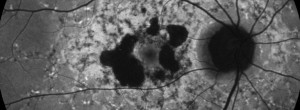

Ensayo clínico OAKS-DERBY: Eficacia y seguridad de pegcetacoplan en el tratamiento de la atrofia geográfica secundaria a DMAE

GALE: seguridad y eficacia a largo plazo del pegcetacoplan en pacientes con AG secundaria a DMAE